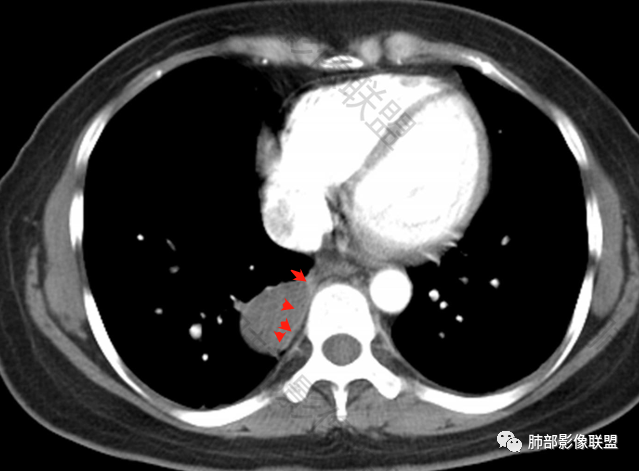

2.右肺下叶脊柱旁类椭圆形块影,边界清楚,密度偏低,隐约见轻度强化囊壁样结构,均匀一致,中央区域未见强化,因属囊样块影。前外缘处显示“壁外”小范围轻度强化软组织密度影,未见磨玻璃晕。

3.块影边缘见匍行血管影,未显示体循环供血。病灶与支气管关系未能显示或呈现。

病灶相邻胸膜轻度强化,未见壁层胸膜侵入或突破。